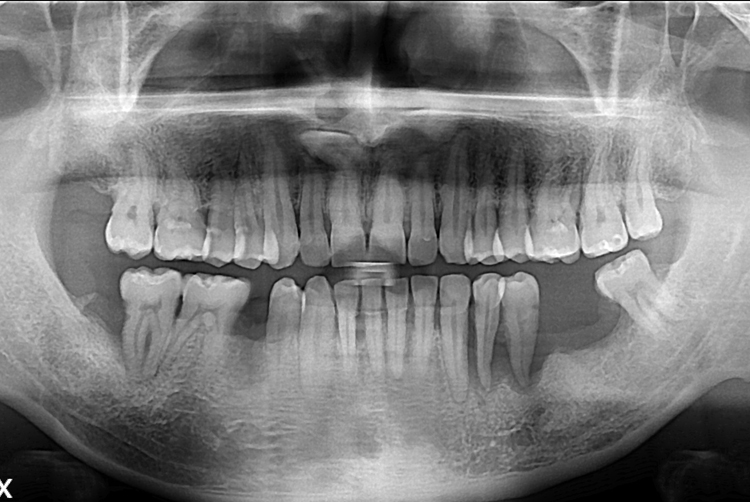

[임플란트] 어금니 임플란트

치료전 : 2019-10-01

세종치과는 많은 환자와 다양한 케이스를 바탕으로

항상 편안한 임플란트 수술을 제공하고자 노력하고,

오래동안 튼튼히 쓸 수 있는 임플란트 수술을 가장 큰 목표로 삼고 있습니다.